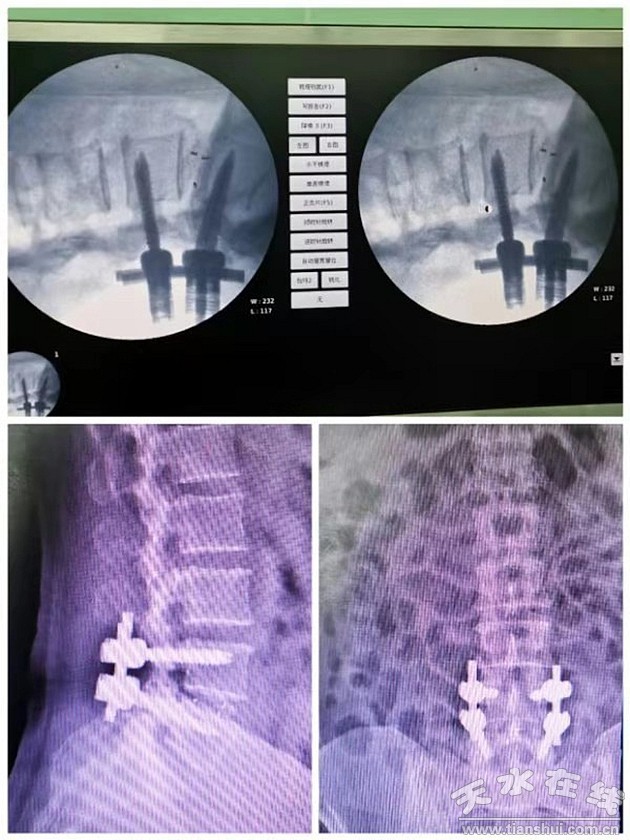

近日,骨科幫扶隊(duì)員郭虎兵醫(yī)生幫助縣醫(yī)院骨科再次開展了一項(xiàng)新技術(shù)——腰椎后路椎體間融合術(shù)(posterior lumbar interbody fusion ,PLIF),術(shù)后效果良好。據(jù)了解,該手術(shù)用于腰椎椎間盤突出癥并椎管狹窄的治療,也屬甘谷縣醫(yī)院首例。

郭虎兵醫(yī)生接診后,經(jīng)過詳細(xì)的診察,診斷為“腰椎椎管狹窄癥、腰4-5椎間盤突出、馬尾神經(jīng)受損”。考慮到患者病程長,癥狀反復(fù)發(fā)作,腰椎間盤突出并椎管狹窄,存在神經(jīng)根及馬尾神經(jīng)受壓的情況,建議手術(shù)治療。由于當(dāng)?shù)赜^念認(rèn)為腰椎手術(shù)風(fēng)險(xiǎn)極高,手術(shù)后會(huì)癱瘓,患者及家人一度懼怕手術(shù),拒絕接受治療。郭虎兵醫(yī)生給患者及家屬耐心講解了疾病及手術(shù)情況后患者及家屬才欣然接受。手術(shù)前經(jīng)過充分的準(zhǔn)備,郭醫(yī)生精心設(shè)計(jì)了手術(shù)方案,打算給患者全麻下施行“腰4/5半椎板切除、PLIF”手術(shù)。10月10日,由郭虎兵醫(yī)生主刀為患者實(shí)施了手術(shù),手術(shù)過程順利。手術(shù)后患者腰痛及左下肢疼痛完全消失,左下肢乏力情況明顯減輕,左下肢及會(huì)陰區(qū)麻木減輕。術(shù)后第3天拔除引流管后患者帶護(hù)具下床活動(dòng),于術(shù)后第7天康復(fù)出院。

腰椎間盤突出癥并椎管狹窄癥為中老年人群比較常見疾病,可以導(dǎo)致神經(jīng)根、馬尾神經(jīng)損傷,患者會(huì)出現(xiàn)頑固性腰腿痛或間歇性跛行癥狀,甚至大小便功能異常,病程長,多反復(fù)發(fā)作,對患者日常生活產(chǎn)生嚴(yán)重影響。臨床治療主要包括保守療法與手術(shù)療法,保守療法主要采用藥物、推拿、按摩等方法,雖然身體損傷小,但治療見效慢、不徹底,整體療效不顯著。因此,大多數(shù)學(xué)者認(rèn)為,對于病程長、癥狀重的患者,一經(jīng)診斷明確,均應(yīng)采用手術(shù)治療,通過手術(shù)減壓來緩解神經(jīng)壓迫癥狀。但是手術(shù)可影響脊柱的穩(wěn)定性,傳統(tǒng)手術(shù)切除腰椎后部結(jié)構(gòu)引起腰椎失穩(wěn)發(fā)生率高,而郭虎兵醫(yī)生本次采用的“半椎板切除PLIF”手術(shù)方式,創(chuàng)傷相對較小,神經(jīng)減壓充分,并發(fā)癥少,能夠維持脊柱穩(wěn)定性且脊髓神經(jīng)功能恢復(fù)良好。而且,該手術(shù)應(yīng)用范圍廣泛,可用于腰椎滑脫癥、腰椎椎管狹窄癥、腰椎間盤突出癥、腰椎椎間關(guān)節(jié)不穩(wěn)等病癥的治療。